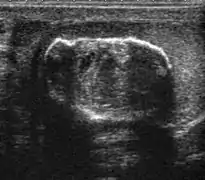

Doppler ultrasound of epididymitis, seen as a substantial increase in blood flow in the left epididymis (top image), while it is normal in the right (bottom image). The thickness of the epididymis (between yellow crosses) is only slightly increased (7 mm).

Doppler ultrasound of the scrotum of the same case, in the axial plane, showing orchitis (as part of epididymo-orchitis) as hypoechogenic and slightly heterogenic left testicular tissue (right in image), with an increased blood flow. There is also swelling of peritesticular tissue.